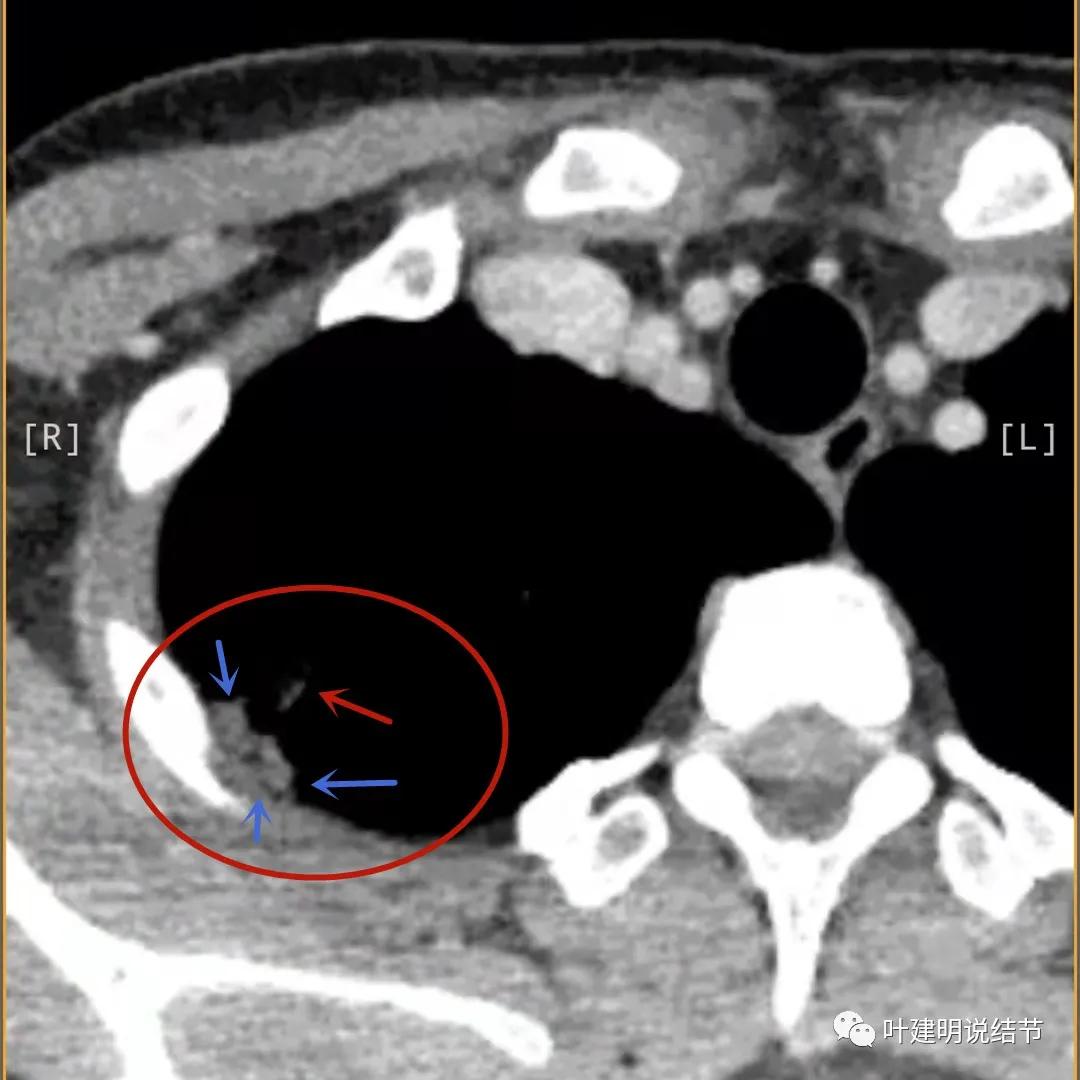

蓝色箭头所指处居然有低密度影,难道是坏死?因为比肌肉密度低,也无强化,况且主病灶的中间也有个低密度的小点状

病灶有明显强化(说明炎性可能性大,如果恶性这样强化,血供丰富,应该倍增速度更快。蓝色箭头示胸膜处低于软组织密度的区域;桔色箭头示病灶边缘平直缺乏膨胀性;黄色箭头示中间的空腔

邻近胸膜处的增厚密度低于肌肉组织,病灶强化明显且均匀

此层也见明显的低密度区域(天蓝色箭头)

胸膜处明显增厚伴低密度区域

天蓝色箭头示病灶低密度区,考虑坏死可能性大,桔色箭头示边缘凹陷无膨胀性

上图示空洞偏心,而且红色箭头所指处与空腔似乎是整合,而非囊壁生长增厚。天蓝色箭头示近胸膜处的低密度区域,考虑坏死成分,囊壁的邻近部分也是极低密度区域,也可能是干酪样坏死区

近胸膜处很厚的软组织

贴胸膜侧也是有强化的,这里可不是结节主病灶所在

薄层影像印象:病灶有明显强化,且邻近胸膜处及部分囊壁区有极低密度区域,考虑干酪样坏死可能性大,肿瘤的坏死可能性小,肿瘤一般要长的比较大,中央缺血性坏死。整体病灶也是觉得散,且邻近胸膜处甚厚。考虑炎性,尤其是肉芽肿性炎伴干酪样坏死可能性大。